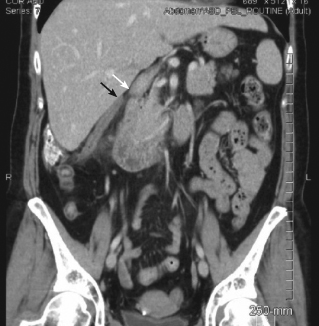

appendicitis

Mohammad R. Mohebbi, MD; Travis R.B. Brownell, MD; Michael L. Wolpert, MD; Marwan F. Jarmakani, MD